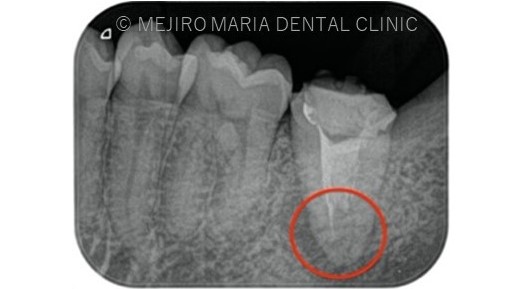

前医にて根管治療を終了したが、痛みと違和感に改善がないため来院された患者様です。前医では樋状根(といじょうこん)の為、これ以上の治療はできないと言われ、抜歯を勧められていました。

根尖性歯周炎は細菌が原因であるため、根管治療にてできる限り細菌を除去することが必要になります。しかしながら、樋状根(Cシェイプ)は根管の大部分が根内部でつながっている形態をしているため(写真2)洗浄が非常に困難です。

また、今回のような樋状根(Cシェイプ)は内側の隆起している部位(写真2赤丸部位)など、歯質が非常に薄い形態をしていることからむやみに削合を行うと穿孔(読み:せんこう パーフォレションともいわれ、歯に穴をあけてしまうことを指す)を起こしてしまう可能性も高くなります。